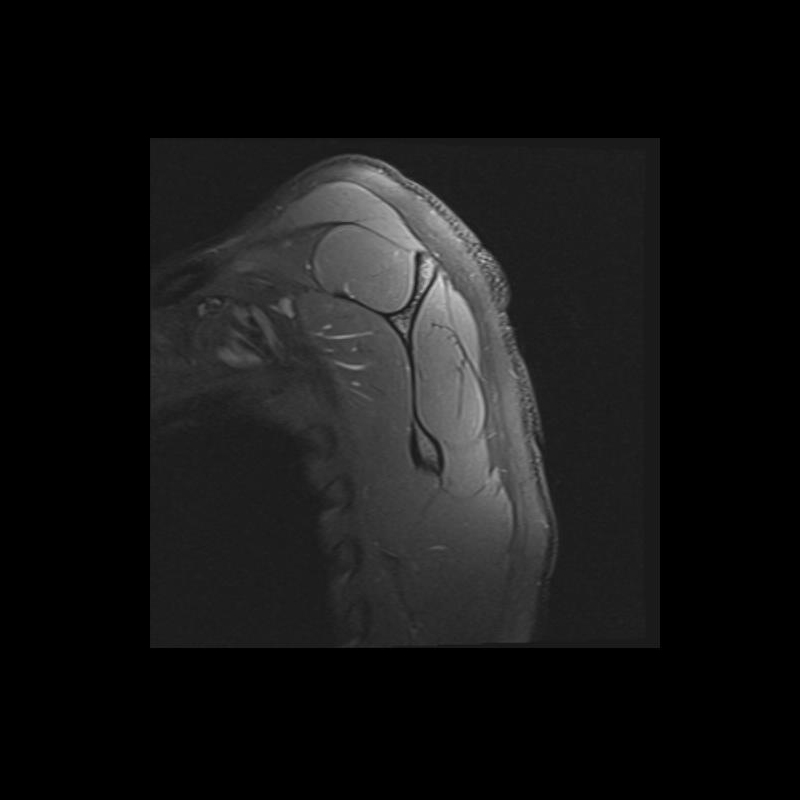

Shoulder MRI Anatomy